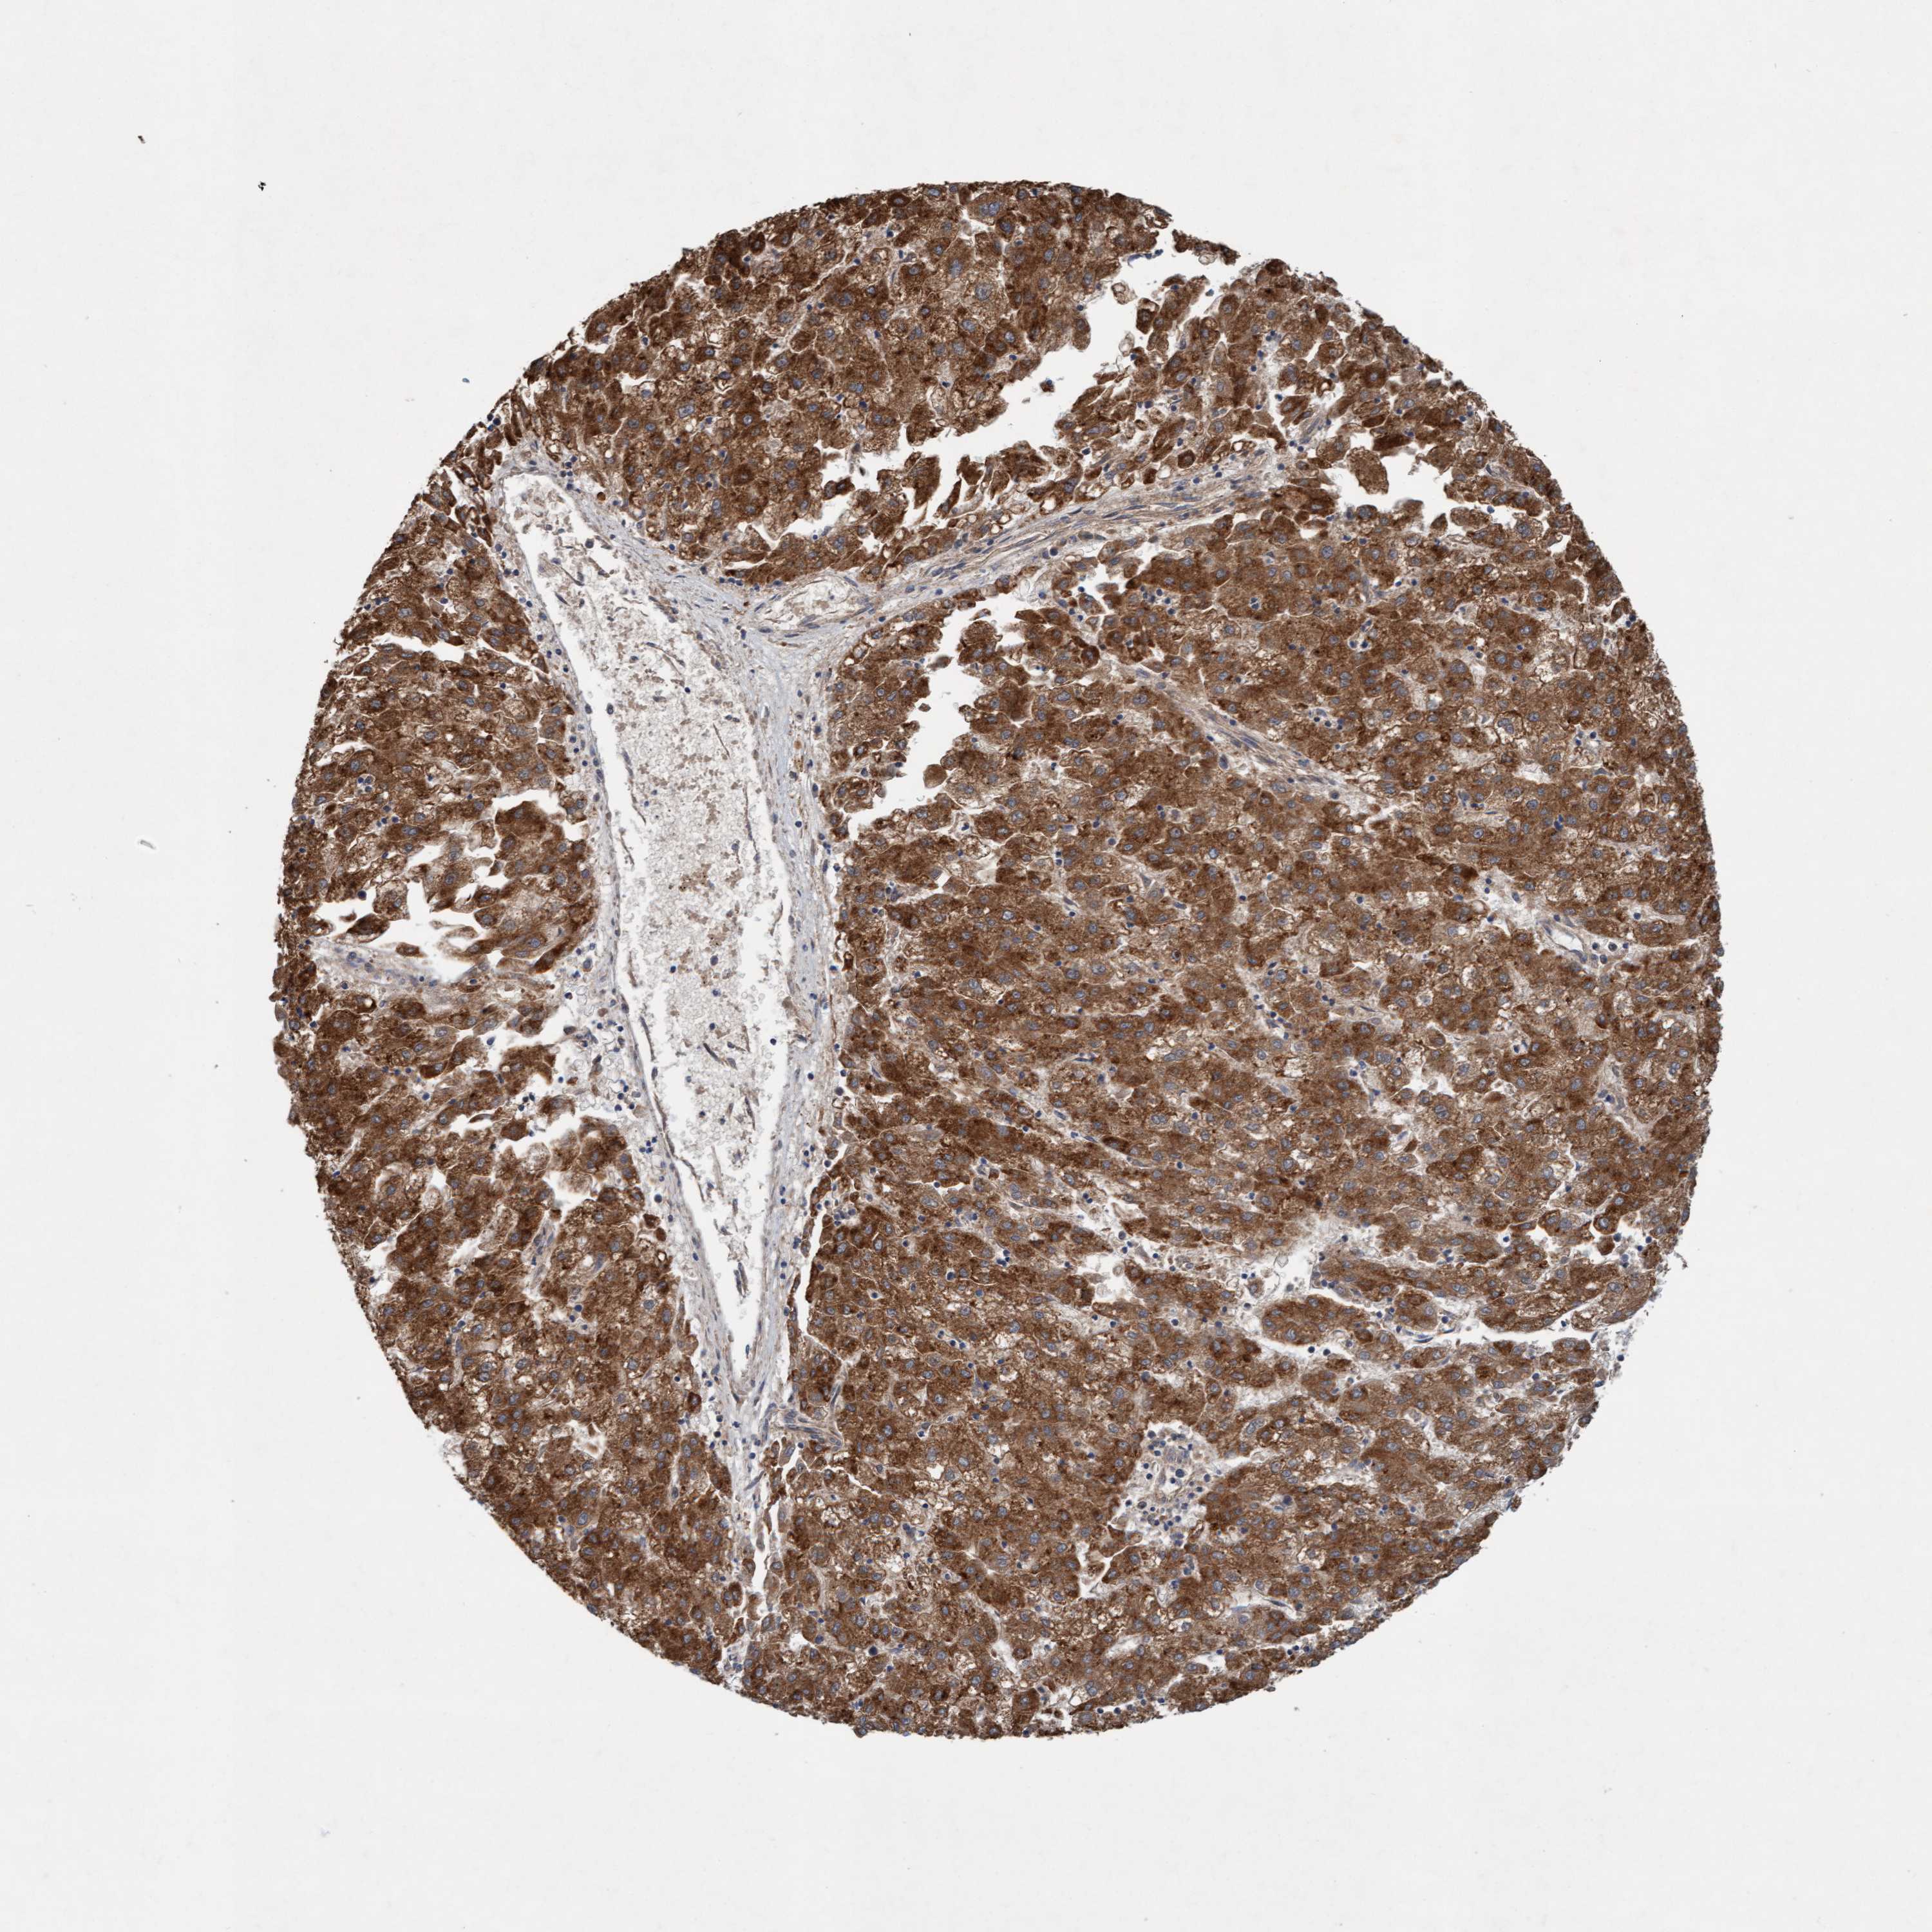

LIVER CANCER - Protein expressioni

A mouse-over function shows sample information and annotation data. Click on an image to view it in a full screen mode. Samples can be filtered based on level of antibody staining by selecting one or several of the following categories: high, medium, low and not detected. The assay and annotation is described here.

Note that samples used for immunohistochemistry by the Human Protein Atlas do not correspond to samples in the TCGA dataset.

Antibody stainingi

Antibody staining in the annotated cell types in the current human tissue is reported as not detected, low, medium, or high, based on conventional immunohistochemistry profiling in selected tissues. This score is based on the combination of the staining intensity and fraction of stained cells.

Each image is clickable and will lead to virtual microscopy that enables deeper exploration of all samples and also displays staining intensity scores, fraction scores and subcellular localization as well as patient and tissue information for each sample.

Antibody HPA021425

Antibody HPA024423

Staining

High

Medium

Low

Not detected

Intensity

Strong

Moderate

Weak

Negative

Quantity

>75%

75%-25%

<25%

None

Location

Nuclear

Cytoplasmic/membranous

Cytoplasmic/membranous,nuclear

Cholangiocarcinoma

Carcinoma, Hepatocellular, NOS